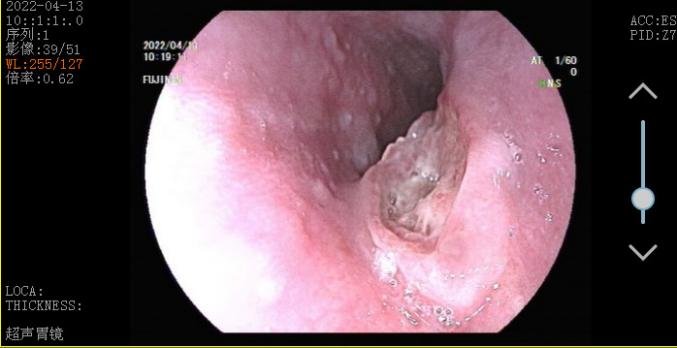

张涛教授接诊后,通过从王叔的主诉,再结合他的症状,第一感觉也认为有点像“食道癌”,建议他住院接受详细检查,入院后第一时间给他做了无痛胃镜检查。检查结果显示,在距门齿27-33cm处,能看见一处黏膜缺损,周围黏膜堤坝样隆起,底批厚苔,单纯从镜下表现看就像是食道癌!

那王叔到底得了什么病差点被认为是癌症?难道这只是普通的溃疡吗?此时张涛提议,“王叔,咱们再做个超声胃镜吧”。超声胃镜可以看到普通胃镜看不到的层面,很快王叔接受了进一步超声胃镜检查,并再次活检。超声胃镜提示1.食管溃疡性质待查(结核?Ca?待病理);2.反流性食管炎(A级);3.慢性非萎缩性胃炎伴糜烂 。